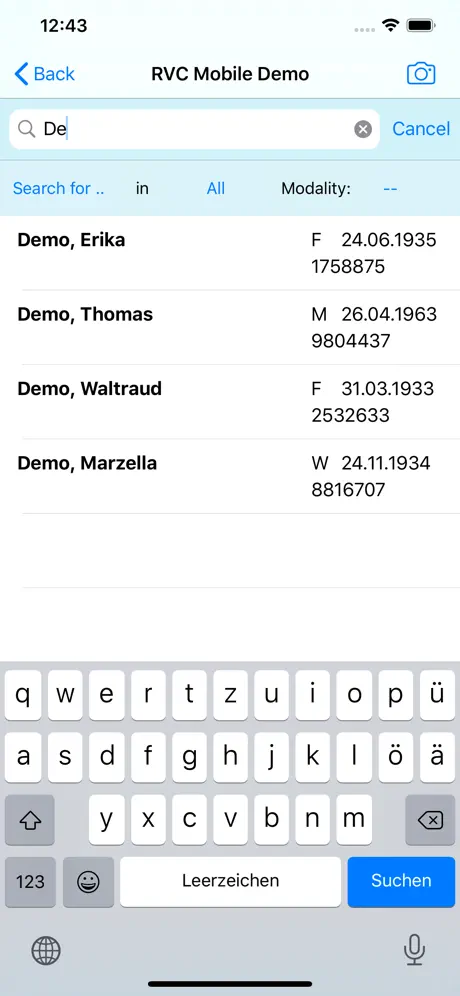

- Patientensuche

- Name, Vorname

- ID

- Geburtsdatum

- Modalität

- Patientensuche

- Name, Vorname

- ID

- Geburtsdatum

- Modalität